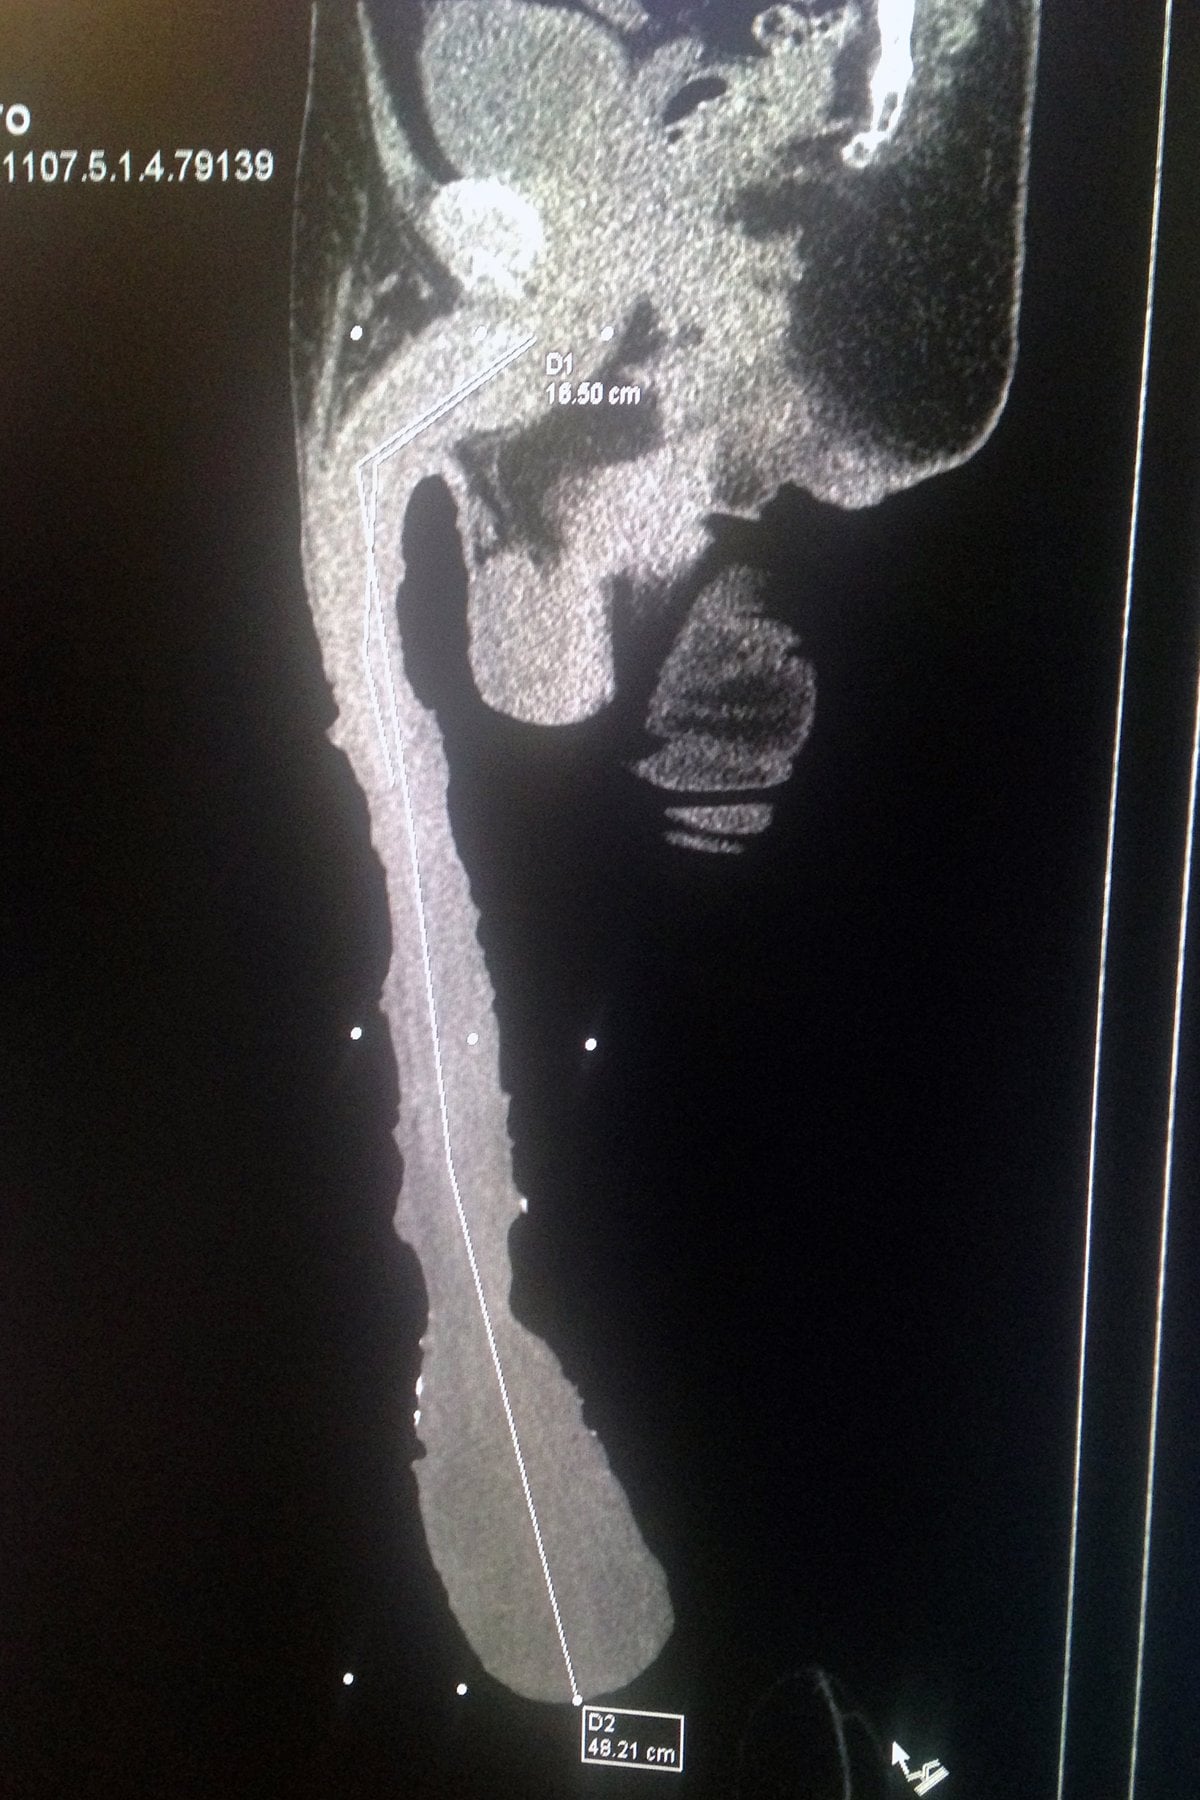

Tudi njegov največji konkurent, 47-letni Jonah Falcon iz New Yorka, ne priznava poraza. Esquivela Cabrero je obtožil, da si je na nedovoljen način (s pomočjo uteži) podaljšal spolni ud. Zdravniki naj bi njegovo teorijo potrdili, kot dokaz pa so opravili tudi rentgenski posnetek.

Mehičan naj bi bil že kot najstnik obseden z dolžino svojega spolnega uda in ga je s pomočjo uteži skozi desetletja skušal še podaljšati.